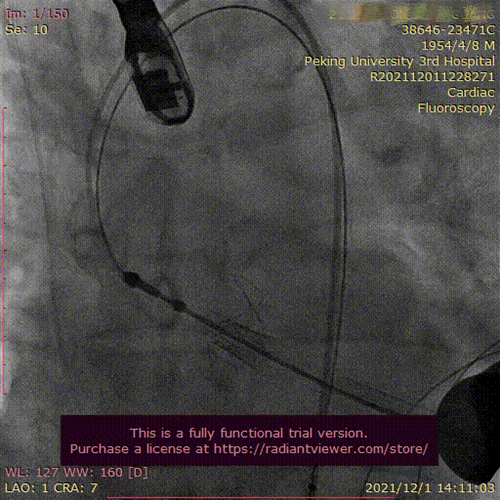

心脏外科完成不停跳小切口多支桥、经导管主动脉瓣置换一站式复合手术

12月1日,北医三院凌云鹏教授团队在心血管内科、麻醉科和手术室的全力配合下,成功为一位冠心病合并主动脉瓣重度狭窄的患者完成不停跳小切口多支桥(MICS-CABG)、经导管主动脉瓣置换(TAVR)一站式复合手术,这种复...